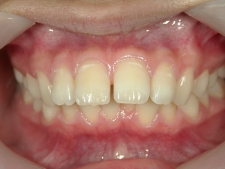

矯正歯科(全顎ワイヤー矯正)治療後

全顎ワイヤー矯正 症例(5)

20歳女性 浜松市東区

在住

治療期間2年4

ヶ月

矯正歯科 治療後